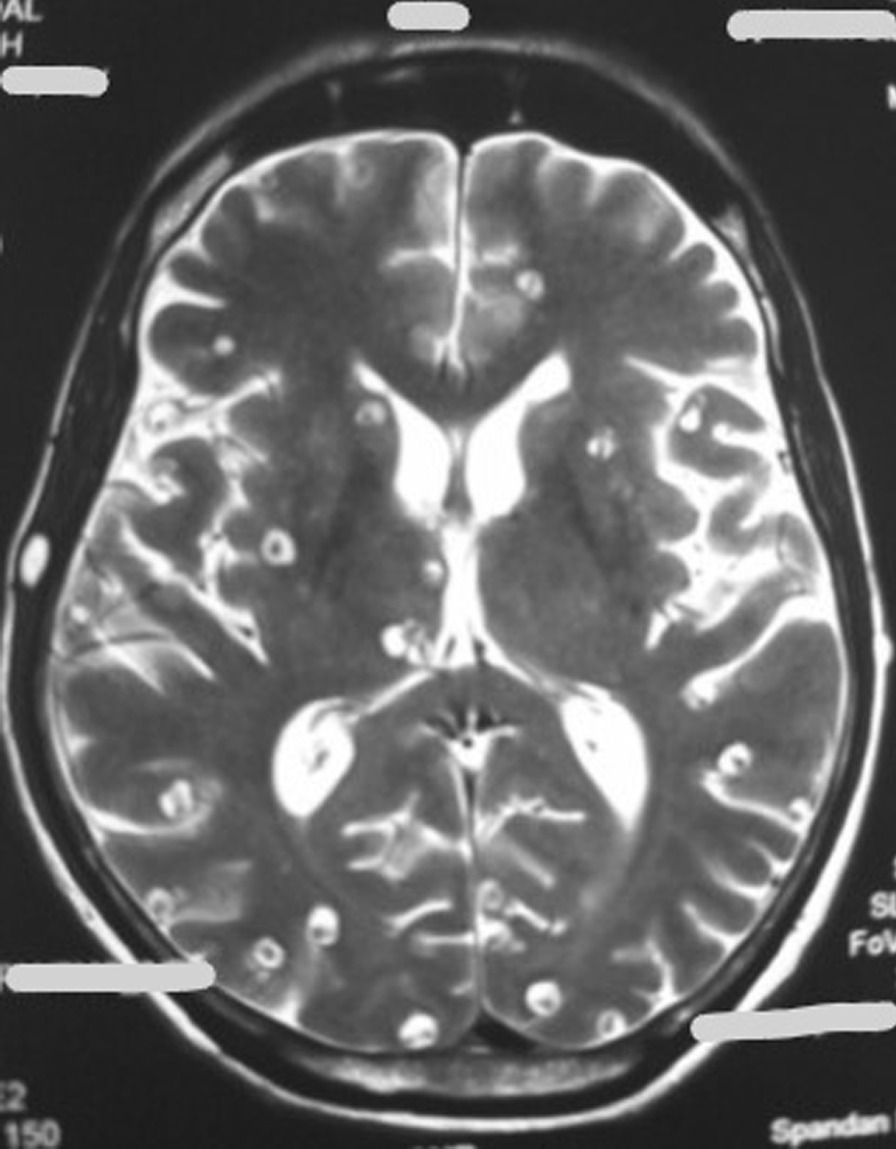

Fig. 3.

Magnetic Resonance Imaging of brain (T2 sequence) showing multiple cysts with scolex contained therein